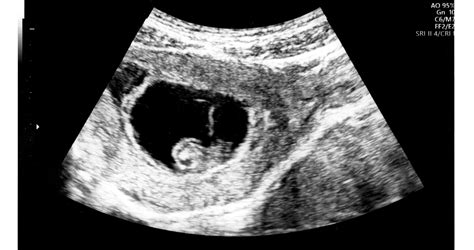

A 12. heti genetikai ultrahang vizsgálat során olyan paraméterek alapján, mint például az orrcsont láthatósága vagy a nyaki redő vastagsága, következtetni lehet a Down-szindróma kockázatára. Fontos azonban tudni, hogy a Down-kóros esetek kb. negyedében nem észlelhetők ultrahangjelek.

Az amniocentézist általában a 15-18. terhességi hét között végzik, de indokolt esetben később is elvégezhető. A vizsgálat során ultrahang vezérlése mellett egy vékony tűvel magzatvizet vesznek az anya hasfalán keresztül. A magzatvízben található sejtekből laboratóriumi vizsgálattal 98-99%-os pontossággal diagnosztizálhatók a leggyakoribb kromoszómális eltérések, mint a Down-szindróma, Edwards-szindróma és Patau-szindróma, valamint számos más genetikai rendellenesség.

A chorionboholy mintavételt (CVS) a 11-14. héten végzik, optimális esetben a 11-13. héten. Ez a méhlepényből (placentából) történő mintavétel, amely szintén ultrahang vezérléssel, hasfalon keresztül történik. A lepény sejtjeiből megerősíthetők vagy kizárhatók a genetikai rendellenességek. A vizsgálat előnye a korábbi diagnózis lehetősége, eredménye egy héten belül megvan.